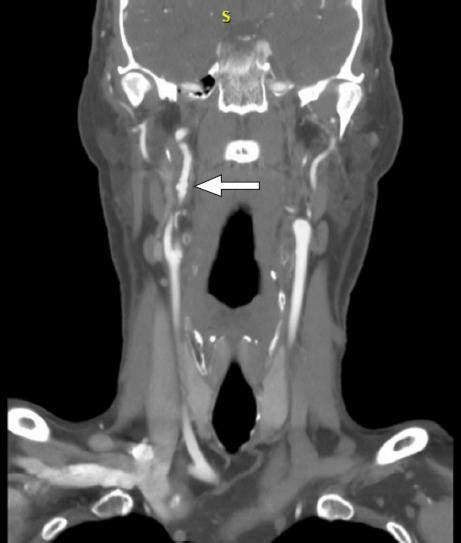

A male patient presented with cardiac arrest attributed to anterior ST-segment elevation myocardial infarction from type 1 spontaneous coronary artery dissection. Subsequent imaging confirmed fibromuscular dysplasia in noncoronary arterial segments. The patient was started on guideline-directed medical therapy and referred to cardiac rehabilitation, showing substantial improvements in clinical status. With greater awareness and advancements in imaging, spontaneous coronary artery dissection has been more frequently recognized, and although as many as 81% to 92% of all cases occur in female patients, it can be seen among men, as well. Adjunctive imaging for arteriopathies may help establish the diagnosis for equivocal causes of acute coronary syndrome in women and men.

Abstract Image